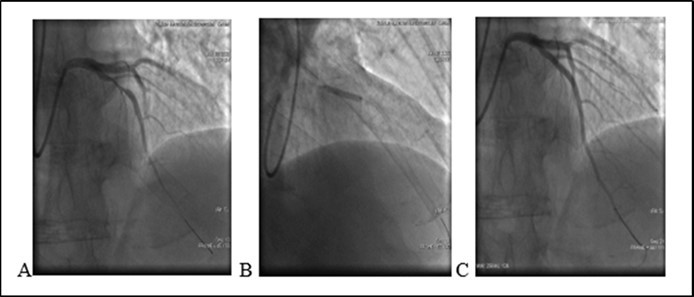

An 46-year old non-diabetic mail without history history of coronary artery disease 08.06.2020 was admitted to the cardiology department of Bokhua Memorial Cardiovascular Center ,with diagnoses of unstable angina (UA). Coronary angiography revealed 80% stenosis in medial segment of Left Anterior Descenting Artery (LAD). One bare metal stent was implanted in the stenotic segment (see Figure 1). The procedure was performed sucssesfully , without any procedure-related complications. After stent placement at hospital patient remaind simptom free. Heamodinamic parameters were stabile and he was discharged from hospital with appropriate prescription.

Figure 1.(08.06.2020) A. Medial stenosis in LAD. B. Stent implantation. C. Final result